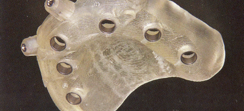

最低4本のインプラントを埋入し、それらを連結し、半日で固定式の仮歯まで入れて審美性、機能性を一日でとりもどせる革新的な治療。

2.歯の形はほぼ天然歯があった時と同じになるので取り外しの義歯に比べて違和感がなく、手入れもインプラントの本数を少なくすることにより、清掃もし易くなっています。